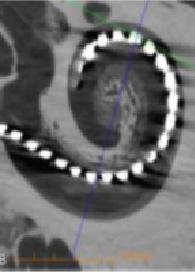

tehnicile chirurgicale erau cele radicale, la ora actuală pe lângă eradicarea bolii prin chirurgie se urmărește și reconstrucția mecanismului auditiv prin proteze pasive de ureche medie, cele mai folosite fiind cele din titan. (Fig. 2). Fiecare pacient este evaluat iar tratamentul este aplicat individualizat în funcție de caracteristicile patologiei. Reabilitarea auditivă este personalizată și în cazurile în care nu se pot realiza prin proteze pasive, utilizându se noile dispozitive moderne, precum implantele cu transmisie osoasă (BAHA, BONEBRIDGE, OSSIA) (Fig. 3) care oferă soluții în cazul pacienților, care în trecut nu aveau speranțe terapeutice. Pe lângă munca cu pacienții, cercetarea clinică reprezintă un loc important în disciplina noastră. Studiile științifice se referă la analizarea rezultatelor tratamentului chirurgical, dar și studii de calitate a vieții pacienților cu otite medii supurate cronice. La acestea se adaugă studiile referitoare la etiopatogeneza bolilor inflamatorii cronice ale urechii medii, în ceea ce privește factorii anatomici precum și unii biomarkeri moleculari implicați. Antrenamentul chirurgical al rezidenților și specialiștilor este un domeniu important în activitatea noastră. Astfel, anual se organizează cursuri de speci-alizare postuniversitare (audiologie, chirurgia surdității și screening auditiv). (Fig. 4) În domeniul patologiei urechii interne se cunoaște faptul că distrugerea celulelor neurosenzoriale din cohlee este ireversibilă la om, iar surditatea neurosenzorială rămâne definitivă. Implantul cohlear este un dispozitiv performant care a schimbat perspectiva copiilor născuți surzi, prin implantare cohleară aceștia fiind capabili să urmeze o școală normală. De asemenea, persoanele suferinde de hipoacuzie profundă își pot recăpăta auzul cu creș-

(Fig. 5, 6)

Fig. 6 Electrod intracohlear după implantare cohleară-imagine computer tomografică